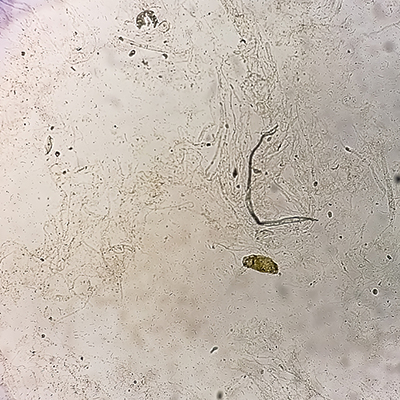

Proteinuria refers to the presence of elevated protein levels in the urine. This condition can arise from various factors, ranging from benign issues such as dehydration or vigorous physical activity to more severe underlying conditions like kidney disease or immune system disorders. Diagnostic testing can verify the occurrence of proteinuria, and an appropriate Proteinuria Treatment in Anantapur strategy can assist in its management.

About Proteinuria